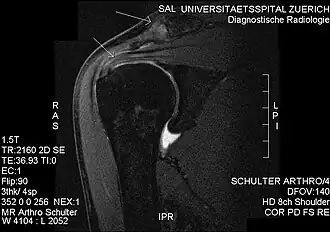

Shoulder impingement syndrome is a syndrome involving tendonitis (inflammation of tendons) of the rotator cuff muscles as they pass through the subacromial space, the passage beneath the acromion. It is particularly associated with tendonitis of the supraspinatus muscle.[1] This can result in pain, weakness, and loss of movement at the shoulder.[2][3][4]